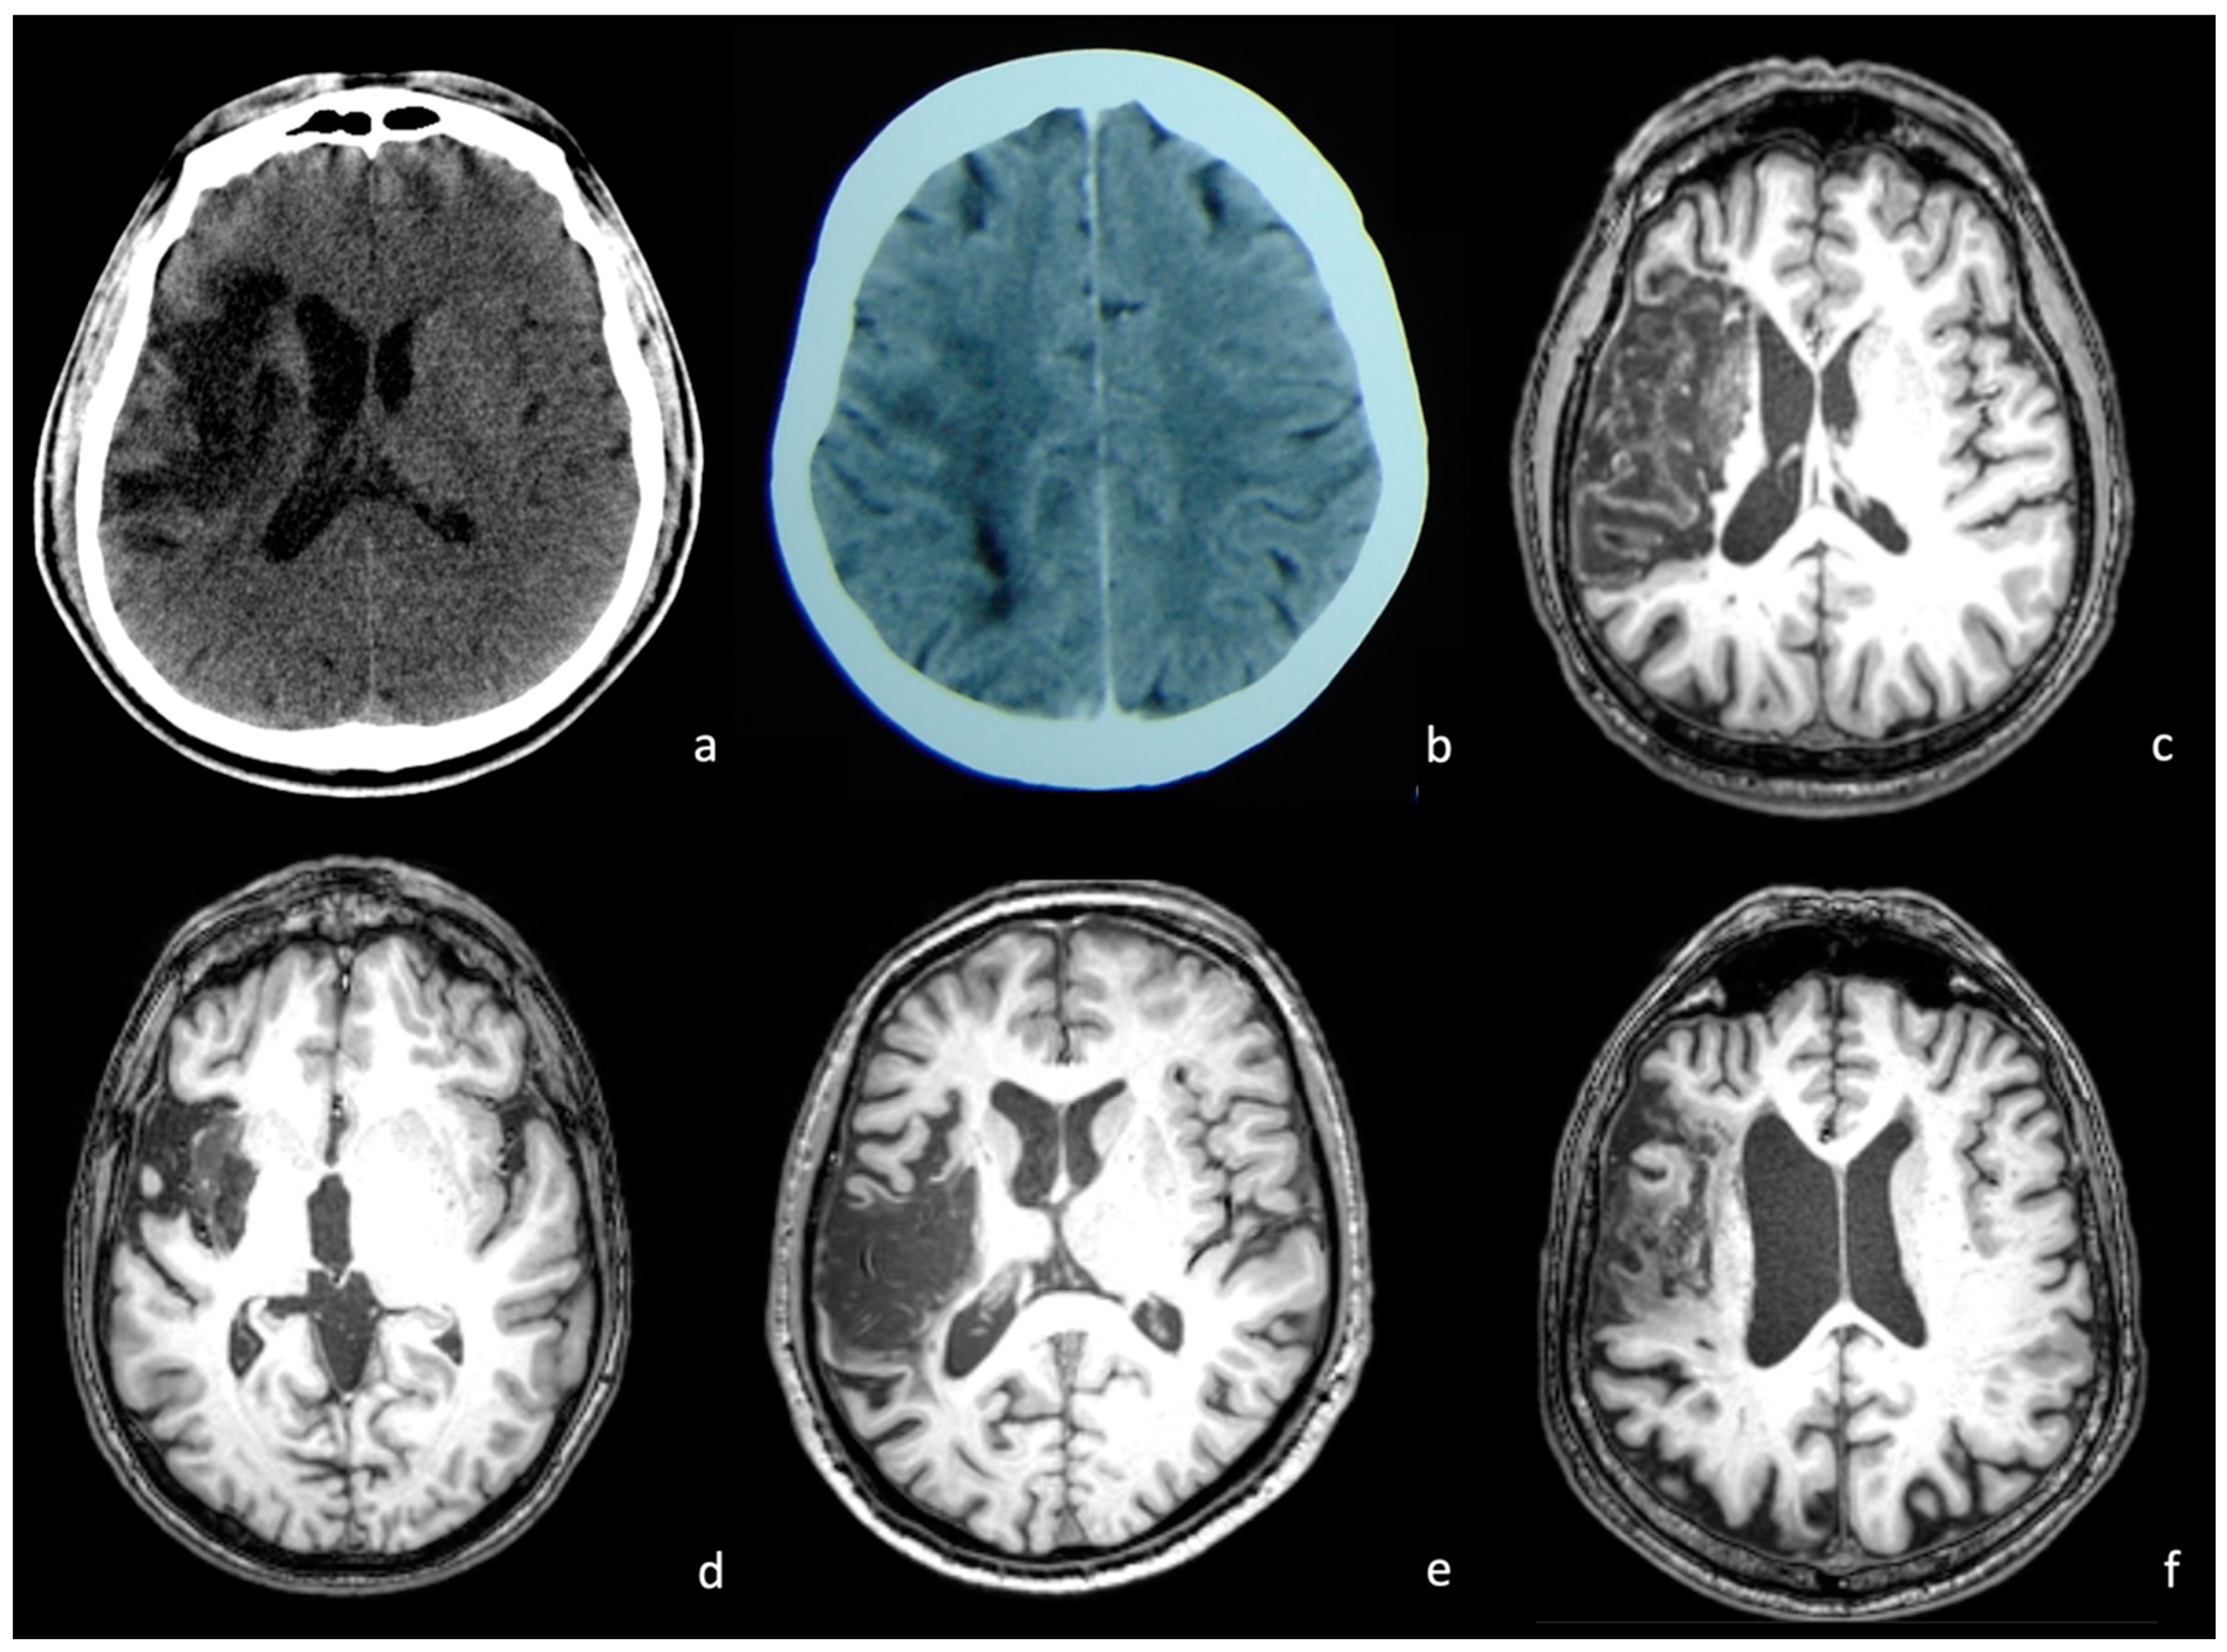

2.2. Neuroimaging Data